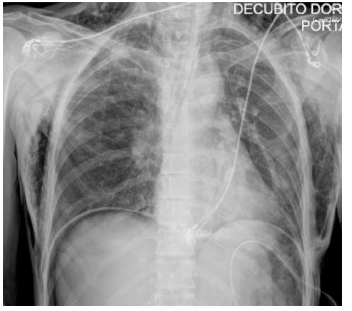

在支气管镜操作室内行胸部X线检查,显示弥漫性肺气肿及气腹(图1)。

随后将患者转运至放射科行计算机断层扫描(CT),结果显示双侧气胸伴广泛性气腹(图2),口服造影剂外渗至腹腔,提示存在胃破裂。CT检查还显示左侧胸腔引流管位于腹腔内。CT扫描后立即于右侧放置胸腔引流管,可见气体即刻排出。